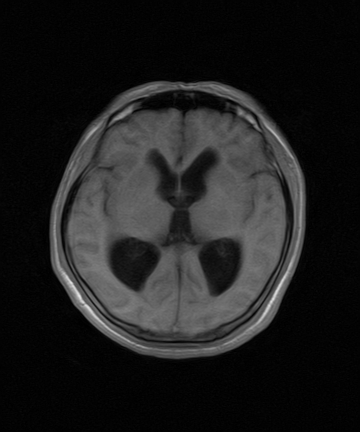

标题: MRI2064:少见病例。男性52,视力下降多年。

四脑室区见混杂信号占位影,脑室系统扩张明显,临近结构显著受压称位,患者52岁,多考虑室管膜瘤可能性大

考虑第四脑室室管膜瘤并阻塞性脑积水。

考虑第四脑室室管膜瘤并梗阻性脑积水;部分性空蝶鞍;左侧上颌窦粘膜下囊肿。

考虑第四脑室室管膜瘤【血供丰富血管母细胞瘤可能】并梗阻性脑积水;部分性空蝶鞍;左侧上颌窦粘膜下囊肿。

小脑蚓部胶质脑膜瘤突入四脑室;肿瘤内见血管流空信号和钙化信号.

比较典型的脉络丛乳头状瘤并脑积水,鉴别小脑蚓部血管母细胞瘤。